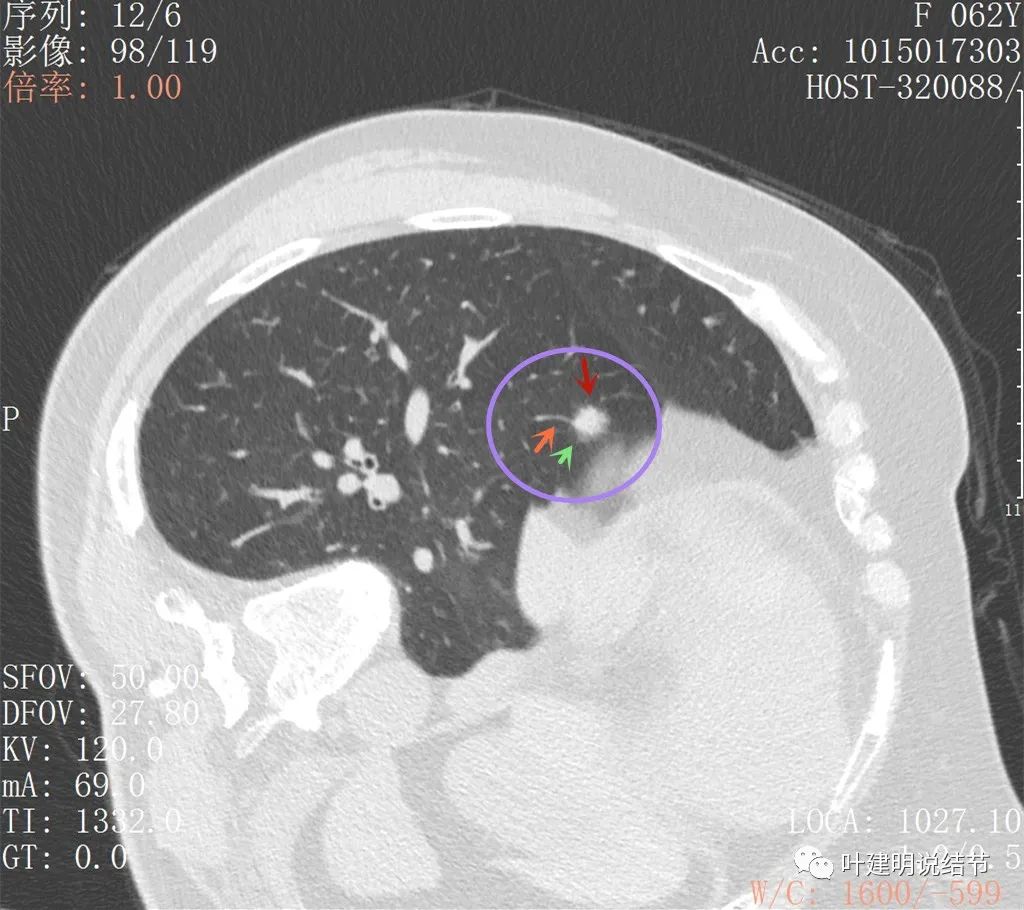

上图也是较为典型的恶性样子,有血管征,有边缘细锯齿状,且存在2年多不吸收好转,也不钙化或成疤痕样收缩

病灶似有毛刺,部分偏长

病灶有毛刺或牵拉的样子,也有少许磨玻璃密度(在边缘部位)